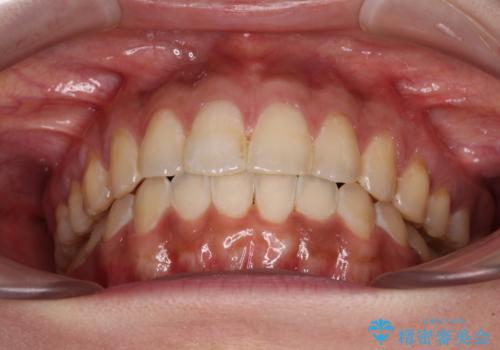

舌のトレーニングをしっかりと行っていただき、上下前歯をしっかりと接触させることができました。

咬合力が強いため、治療途中に奥歯が咬み合わない期間が続きましたが、上下の奥歯でゴムかけを行っていただき、違和感なく咬み合うように仕上げることができました。